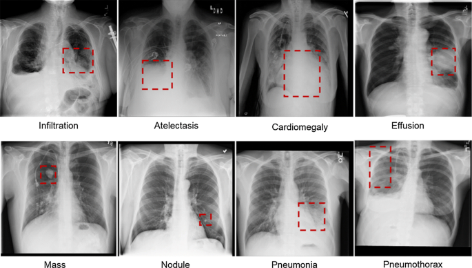

Service as neural network model for assisting radiologists in classifying chest X-rays as either showing or not showing signs of pneumonia, using deep learning techniques to enhance accuracy and speed up the diagnosis process. Number of words

Tech stack: Python, Scikit-Learn, Seaborn, Matplotlib, TensorFlow, Keras, and OpenCV.